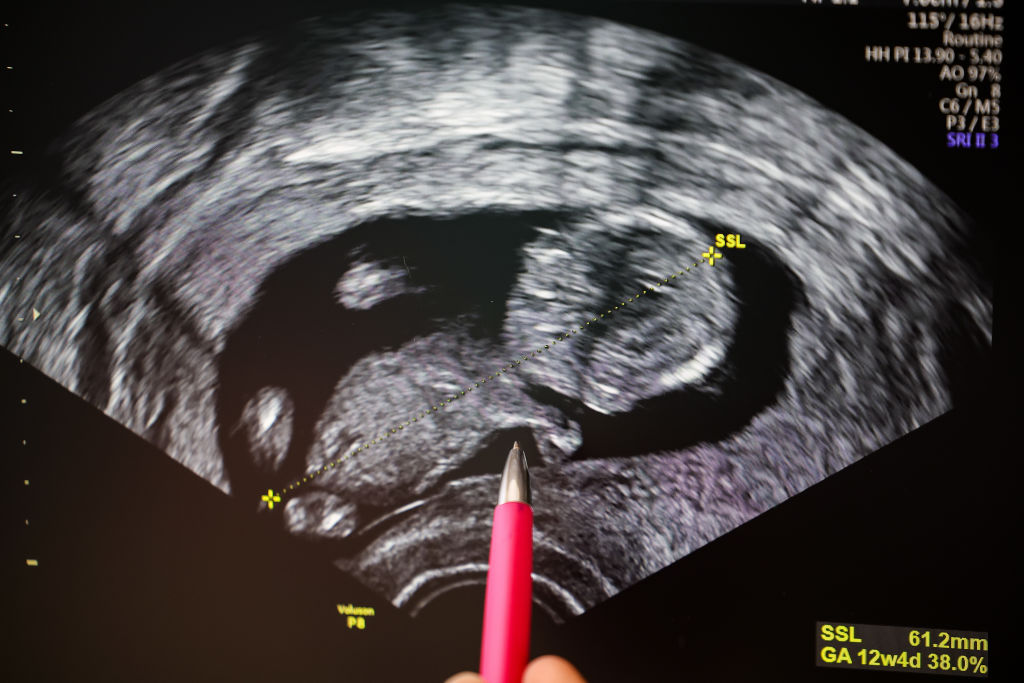

A második trimeszter ultrahangfelvételei már sokkal részletgazdagabbak. Ekkor láthatóvá válik a baba arca, gerince és belső szervei, az úgynevezett genetikai ultrahang pedig segít kiszűrni az esetleges rendellenességeket. A modern technológiának köszönhetően akár 3D vagy 4D képek is készülhetnek, amelyek szinte élethűen mutatják meg a magzat arcvonásait és mozdulatait.